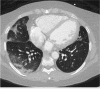

Since early 2020, the world has been facing a pandemic caused by the novel coronavirus SARS-CoV-2. Although this positive single-stranded RNA virus primarily causes pulmonary infection and failure, it has been associated with multiple cardiovascular diseases including troponin elevation, myocarditis, and cardiac arrhythmias. Cardiac patients are susceptible to developing more severe infection from SARS-COV-2, making management complicated. In this review we discuss the cardiac manifestations of COVID-19 infections as well as considerations for the management of primary cardiac pathologies during this pandemic.